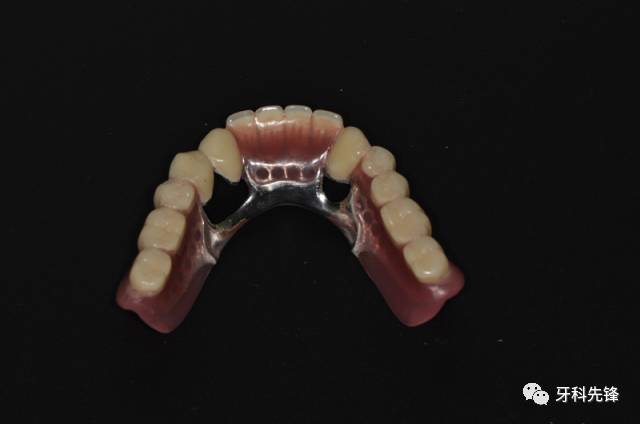

【病例】全口双套冠修复

图片尺寸640x424

详解什么是套筒冠义齿以及套筒冠假牙的优缺点和制作过程

图片尺寸835x471